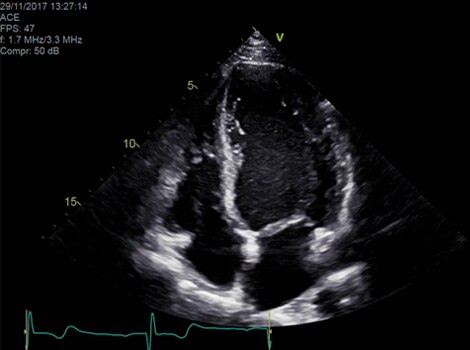

Vivid 产品组合

心脏自动多普勒可自动提供多普勒测量结果,以最小的用户指导获得常见参数。了解更多信息

Vivid E95

cSound™ 波束形成技术可实现卓越的可视化质量,同时在 2D、彩色血流、多普勒和 4D 格式的分辨率令人惊艳。了解更多信息

VividTM 系列心脏超声波自动功能成像(AFI)

明确评估左心室功能和心脏功能,提高临床信心。了解更多信息